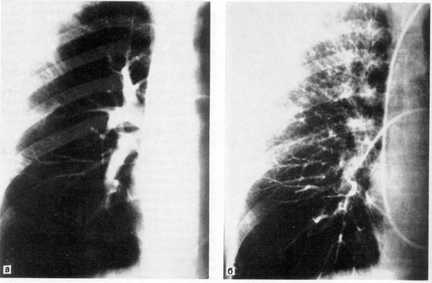

Рис. 7. Селективная ангиография бронхиальных артерий.

При селективной ангиографии бронхиальных артерий катетер вводится в грудную аорту и далее — до устья бронхиальных сосудов; введение контрастного вещества осуществляется с помощью автоматического инъектора. Сериография, проводимая, как правило, в переднезадней проекции, может быть дополнена рентгенограммами в боковой или косой проекциях в зависимости от задач исследования (рис. 7).

При анализе бронхиальных ангиограмм определяются уровень и тип анатомического ветвления сосудов, положение, форма, диаметр, характер контуров сосуда, извитость его и проходимость, характер и уровень окклюзии, степень развития коллатеральных ветвлений и их взаимосвязь с легочной артерией. Учитываются уровни анастомозирования двух систем кровообращения легких (субсегменты, сегменты, доли или л

обулярные ветви легочной артерии).